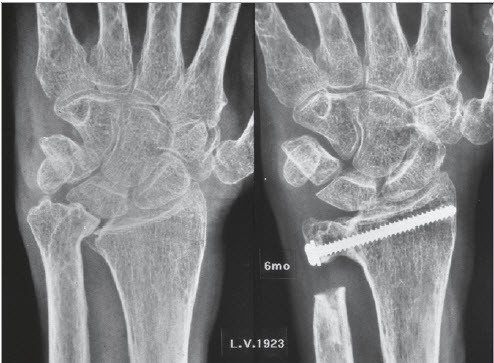

Bei einer isolierten Arthrose des unteren Speichen-Ellen-Gelenks (DRUG) findet sich vor allem eine schmerzhafte und eingeschränkte Vorderarm-Rotation. Die Beugung und Streckung im Handgelenk ist nicht oder nur minimal betroffen. In diesen Fällen wird eine isolierte Teilversteifung des Gelenkes nach Sauvé- Kapandji durchgeführt (Abb. 2). Bei diesem Eingriff wird das Ellenköpfchen mit der Speiche verbunden. Um die Vorderarm- Drehbewegung gleichwohl erhalten zu können, ist es erforderlich, ein Knochenstück der Elle herauszunehmen. Dieser Eingriff hat sich bewährt in Fällen, in denen das Gelenk isoliert zerstört worden ist. Eine solche Zerstörung kommt bei gewissen Formen der chronischen Polyarthritis vor, ferner auch als Folge von Speichenbrüchen.

Das Ellenköpfchen wird meistens mit einer Schraube zur Speiche fixiert. Diese Fixation ist nur bedingt übungsstabil, weshalb eine zusätzliche äussere Fixation in Form einer abnehmbaren Schiene erforderlich ist. Nach der Operation bleiben sowohl die Handgelenkbeweglichkeit als auch die Unterarm-Rotation in der Regel erhalten.